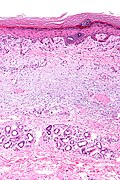

Micro

The sections show a raised lesion with compact hyperkeratosis and irregular acanthosis. Spongiosis is seen focally. There is minimal hypergranulosis.

There is no thinning of the suprapapillary plate and no dilated superficial blood vessels. There is no interface activity.